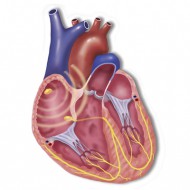

Szív vezetési rendszer képviseli idegrostok keresztül impulzusvezetés lépés egy szigorúan meghatározott irányban - a pitvarok a kamrákba. Ez biztosítja szinkron munka minden kamarák a szív. Ha akadályokba ütközik a szívizomban (hegek, például), további kötegek alakult méhen belül, összehúzó mechanizmusok törött és vannak előfeltételei a ritmuszavar.

- Teljes atrioventricularis blokkot. ha egy impulzus a pitvar eléri a kamrák;

- Transzformálása hiányos blokád teljes egészében;

- Rohamokban jelentkező tachycardia. kamrafibrilláció. amikor zuhan összehúzódó a szívizom;

- Tachycardia, bradycardia, mint 200 kevesebb, mint 30 percenkénti szívverések.